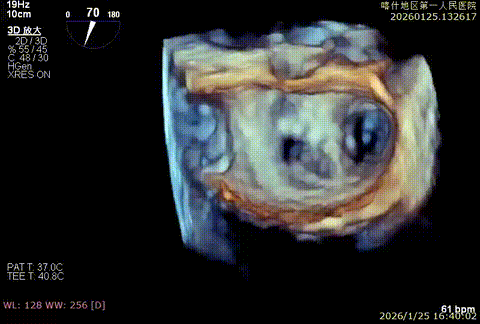

该例患者为VFMR,术前制定手术策略:患者二尖瓣重度反流,后叶严重栓系,心房心室扩大。患者瓣口面积4.5cm2,预计使用两枚XTR解决患者瓣叶脱垂和反流。考虑到先于2区进行钳夹,应该能获得足够的房间隔穿刺高度。术中经不断调整穿刺位点,最终穿刺高度4.4cm。成功穿刺后将第一枚XTR送入二尖瓣正上方,进行弹道测试Orientation调整后,最终定位于2区正上方下左心室。第一枚夹子在左室成功捕捞和钳夹瓣叶后,瓣叶反流程度显著降低,夹子外侧仍见部分反流,随后在第一枚夹子外侧再次放置一枚XTR,瓣叶反流程度进一步降低至微量。通过TEE观察,二尖瓣双孔组织桥稳定,跨瓣压差3mmHg,肺静脉逆流改善明显,手术安全结束。

3D enface后叶栓系

3D enface观察反流